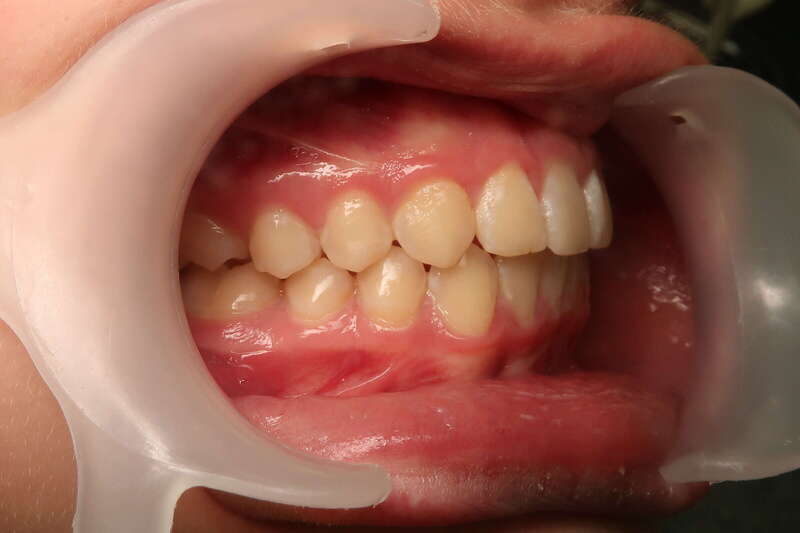

Cas n°1 traité par aligneurs (interception) - enfant

Ce cas d’interception chez un enfant de 8 ans démontre l'efficacité des aligneurs pour corriger des troubles fonctionnels précoces. Le diagnostic présentait des inversions d'articulé provoquant une déviation de la mandibule vers la gauche et un décalage des milieux.

Grâce à une coopération exemplaire et un traitement totalement indolore, l'expansion de l'arcade a permis de recentrer la mâchoire. Cette intervention a littéralement remis la croissance sur les rails, neutralisant le risque d'asymétrie faciale squelettique.

• Correction fonctionnelle : Recentrage immédiat de la mandibule et des milieux inter-incisifs.

• Prévention : Création d'un environnement favorable pour les dents définitives à venir.

• Bien-être : Approche douce respectant le confort de l'enfant.

C'est une étape fondamentale qui simplifie l'avenir orthodontique du patient tout en garantissant un développement facial harmonieux.